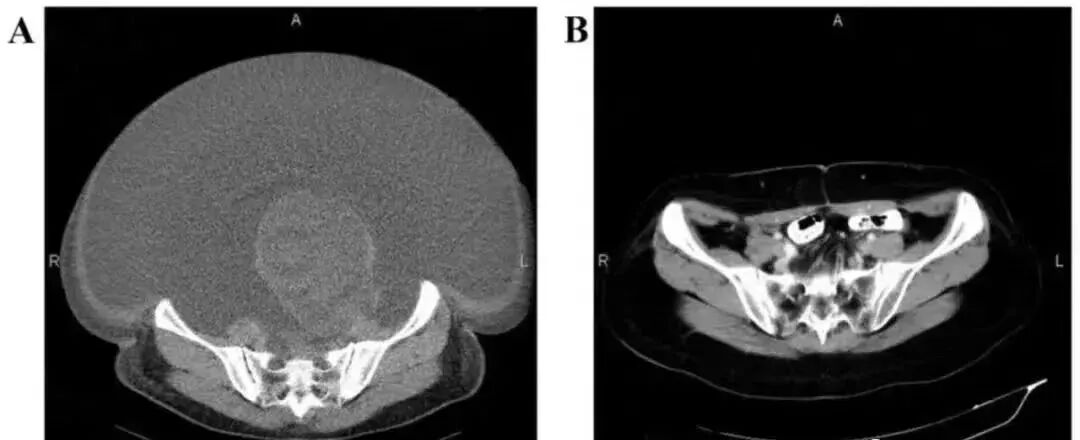

案例2:国内一名60岁的卵巢癌晚期患者,在接受了体外扩增,高度活化的同种异体NK细胞的治疗后,CA125水平从11,270降至580,所有腹水都消失了。此外,CT扫描的肿块体积减小,并且没有出现副作用。

△  NK细胞治疗前和治疗期间的CT扫描结果